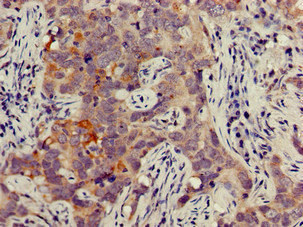

Immunohistochemistry of paraffin-embedded human pancreatic cancer using CSB-PA01949A0Rb at dilution of 1:100